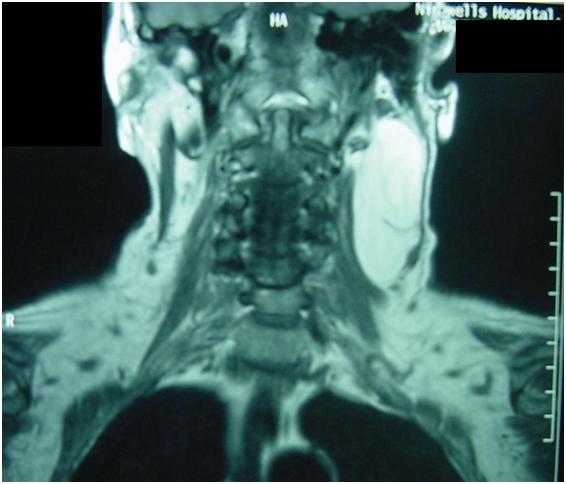

Large lipoma of the neck | Image | Radiopaedia.org

Optimal Imaging of Infiltrating Lipomas of the Neck – MedCrave online

Giant lipoma arising from deep lobe of the parotid gland | World …

Optimal Imaging of Infiltrating Lipomas of the Neck – MedCrave online